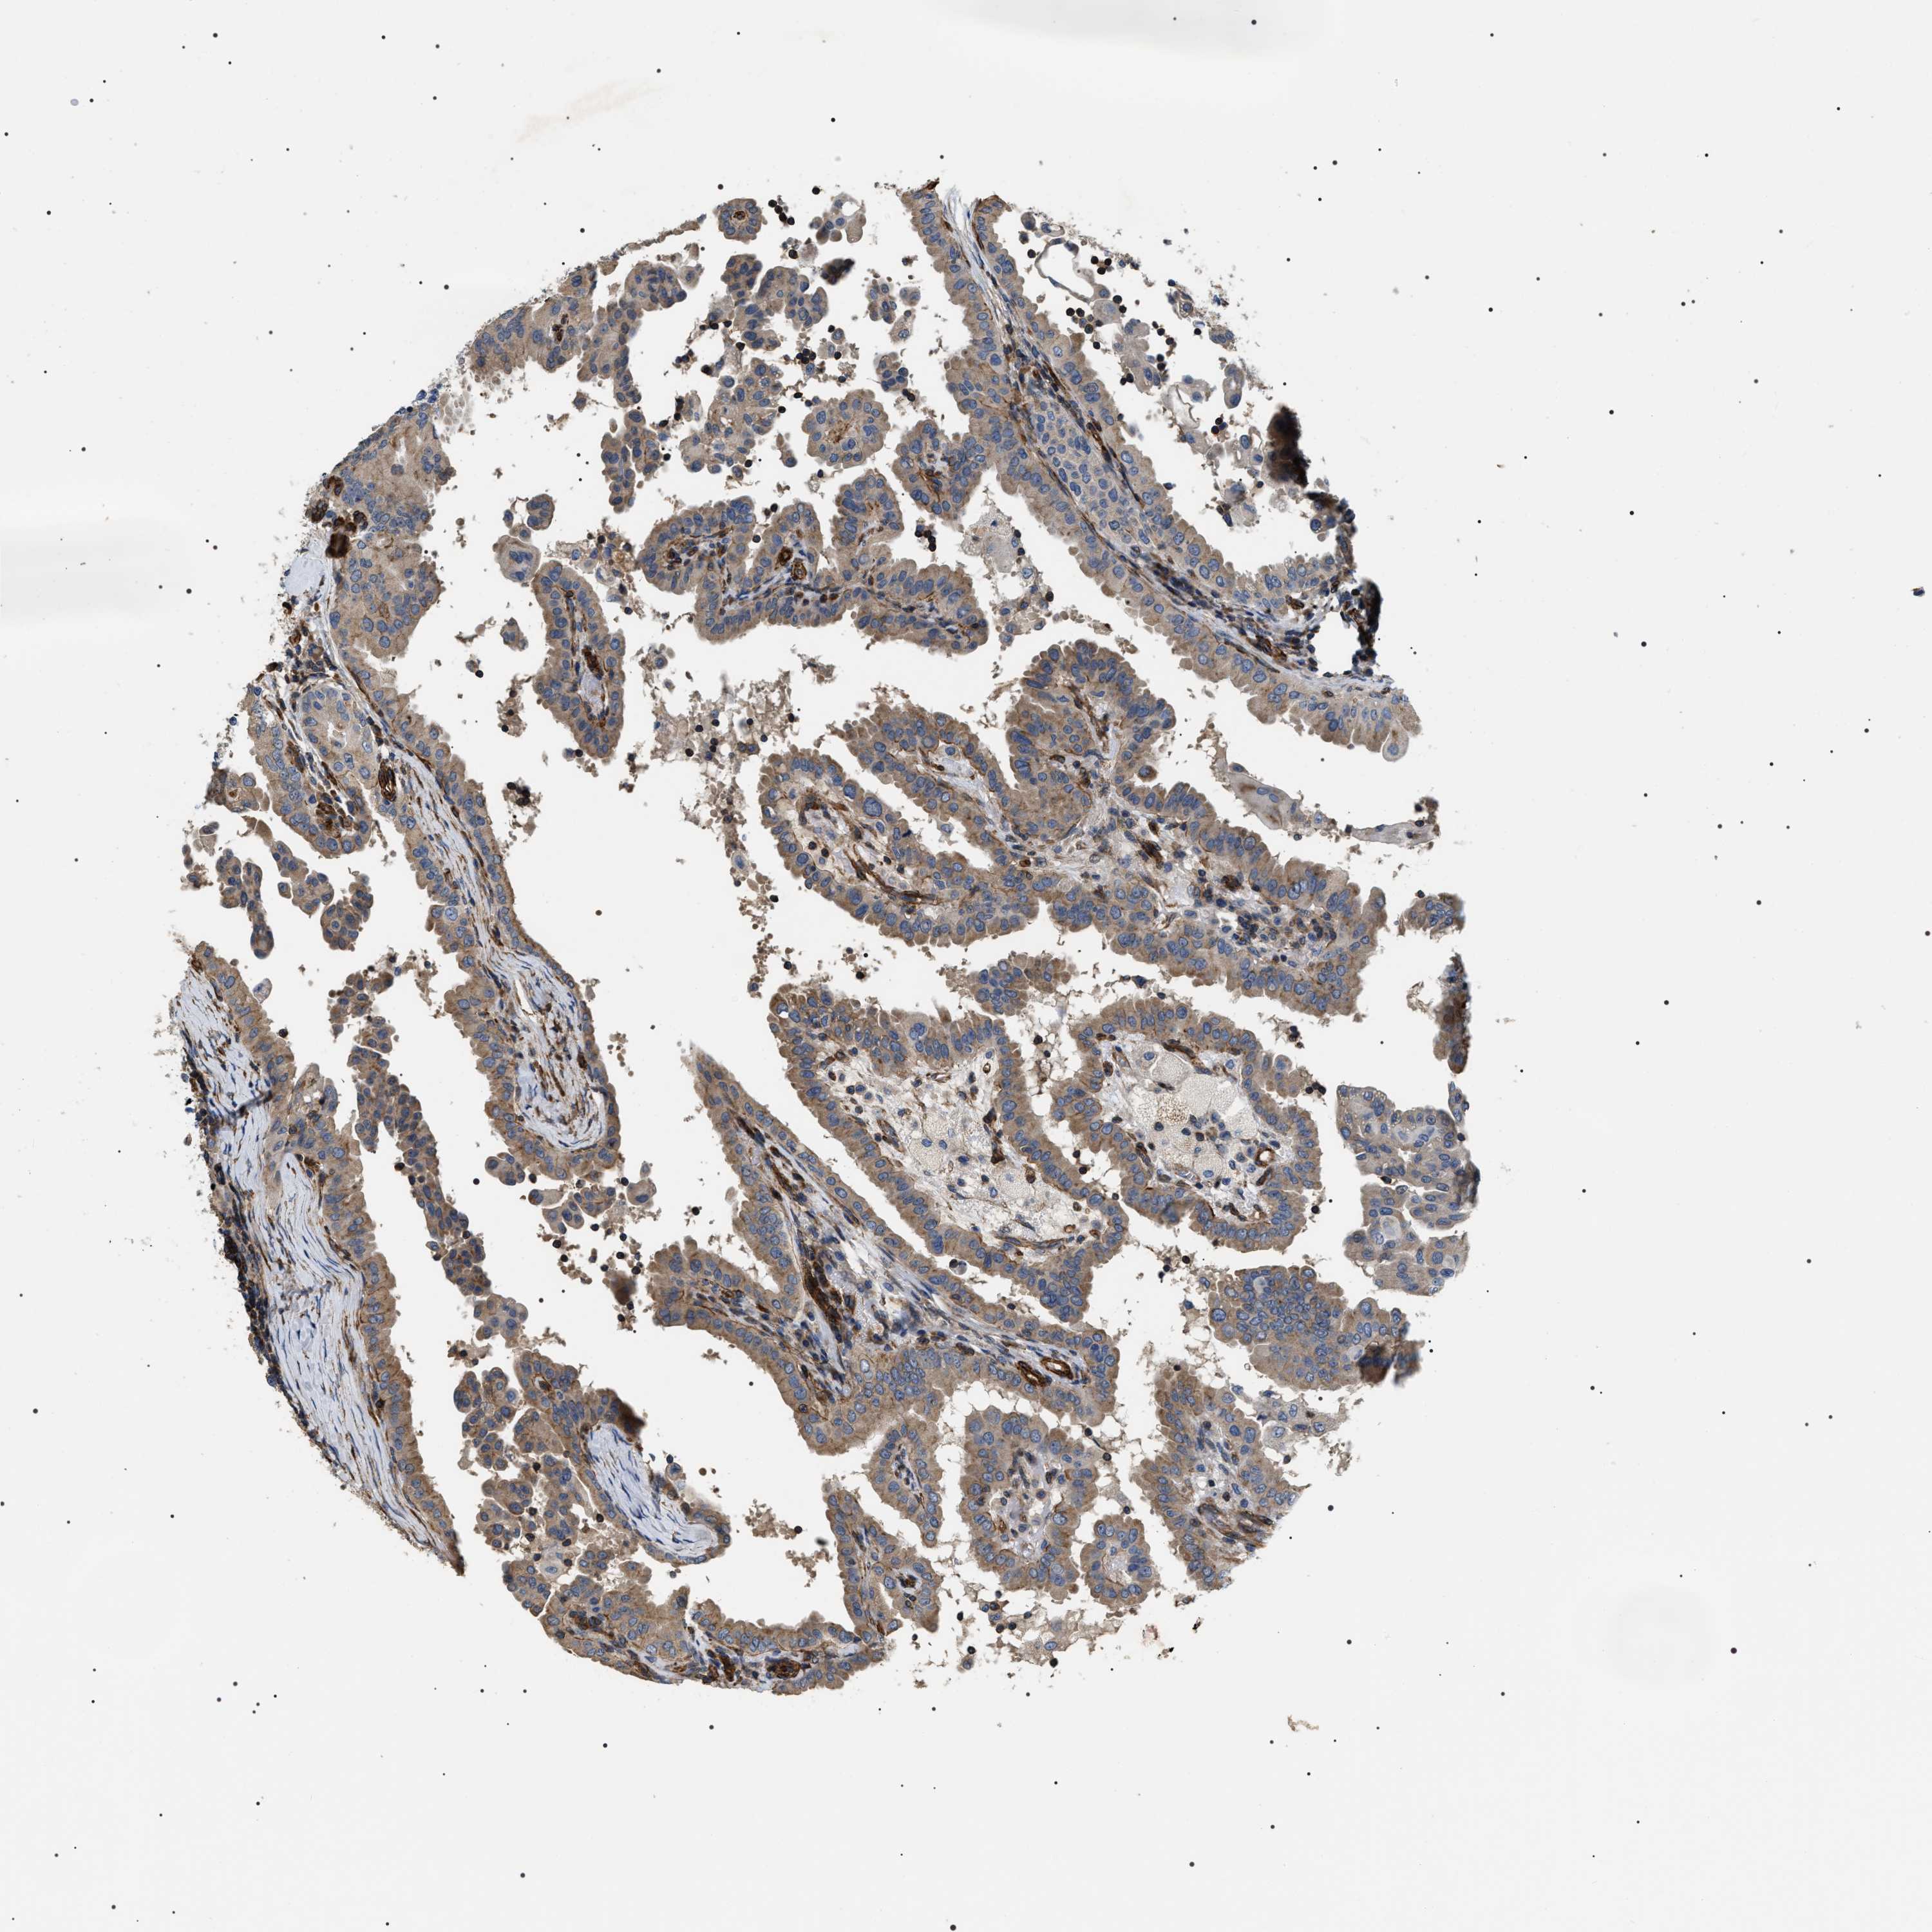

THYROID CANCER - Protein expressioni

A mouse-over function shows sample information and annotation data. Click on an image to view it in a full screen mode. Samples can be filtered based on level of antibody staining by selecting one or several of the following categories: high, medium, low and not detected. The assay and annotation is described here.

Note that samples used for immunohistochemistry by the Human Protein Atlas do not correspond to samples in the TCGA dataset.

Antibody stainingi

Antibody staining in the annotated cell types in the current human tissue is reported as not detected, low, medium, or high, based on conventional immunohistochemistry profiling in selected tissues. This score is based on the combination of the staining intensity and fraction of stained cells.

Each image is clickable and will lead to virtual microscopy that enables deeper exploration of all samples and also displays staining intensity scores, fraction scores and subcellular localization as well as patient and tissue information for each sample.

Antibody HPA020386

Staining

High

Medium

Low

Not detected

Intensity

Strong

Moderate

Weak

Negative

Quantity

>75%

75%-25%

<25%

None

Location

Nuclear

Cytoplasmic/membranous

Cytoplasmic/membranous,nuclear

Papillary adenocarcinoma, NOS

Follicular adenoma carcinoma, NOS